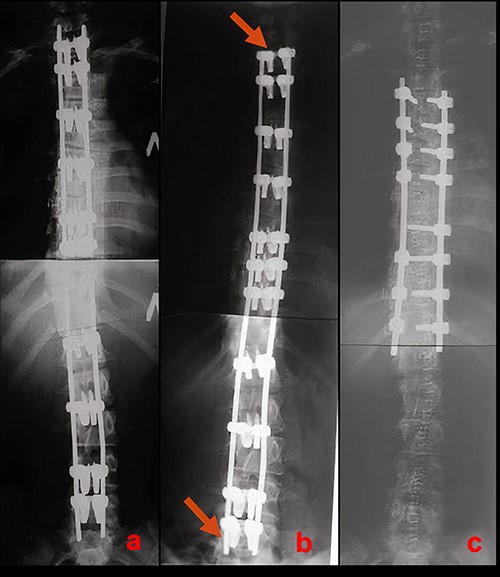

On 10-year follow-up, radiographs of the spine in the standing position in 2021 adequate correction are preserved with a slight asymptomatic increase of lumbar deformity (Figs 4 and 5).

X-rays of the patient’s spine at a 10-year follow-up. (a) AP X-ray of the spine in standing position. There is a slight increase in the lumbar curve. (b) Lateral X-ray of the spine in standing position.